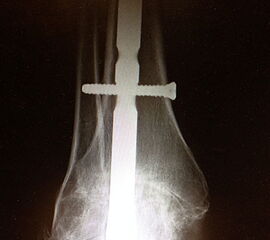

Erreichen eines schmerzfreien oberen Sprunggelenkes mit belastbarem und plantigrad aufsetzbarem Fuss (Abb. 1a und b) unter Verzicht auf die Bewegungsfunktion des oberen Sprunggelenkes. Operative Resektion der arthrotisch veränderten Gelenkflächen bis in den subchondralen frischen Knochen von Tibia und Talus. Fusion mittels Kompressionsschrauben oder Arthrodeseplatten, bedarfsweise Arthrodesenagel.

Abbildung 1b